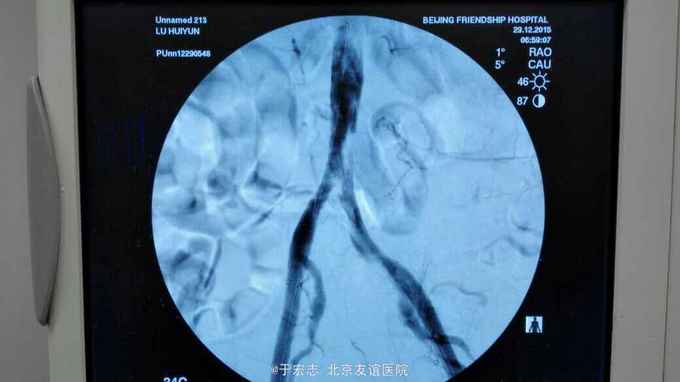

男性76岁,腹主动脉骑跨栓塞,经外院ct证实,病程3天,转至我院。

查体,双下肢大片皮肤青紫,双小腿无感觉,双股动脉波动消失

全腔内技术操作,用8F rotarex机械取栓导管操作,术前留置股静脉鞘,边操作边放静脉血,减少毒素吸收。静脉血经自体血回收处理。 操作完成后以血管缝合器缝合股动脉穿刺点,加压包扎。 患者转重症医学科途中出现心跳骤停,于手术室心外按压2小时复苏成功,转重症医学科血滤治疗。术后五小时生命体征均可维持,但家属还是放弃进一步治疗转运回当地治疗。